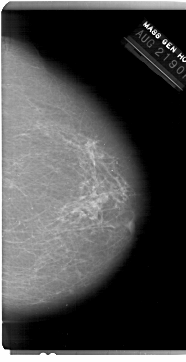

A_1215_1.LEFT_MLO

DATE_OF_STUDY 21 8 1990

PATIENT_AGE 66

FILM_TYPE REGULAR

DENSITY 2

DIGITIZER HOWTEK 43.5

LEFT_MLO LINES 6871 PIXELS_PER_LINE 4021 BITS_PER_PIXEL 12 RESOLUTION 43.5 OVERLAY